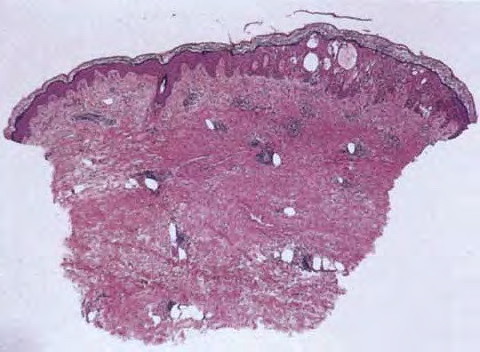

Acute contact dermatitis = التهاب ا لجلدالحاد بالتماس